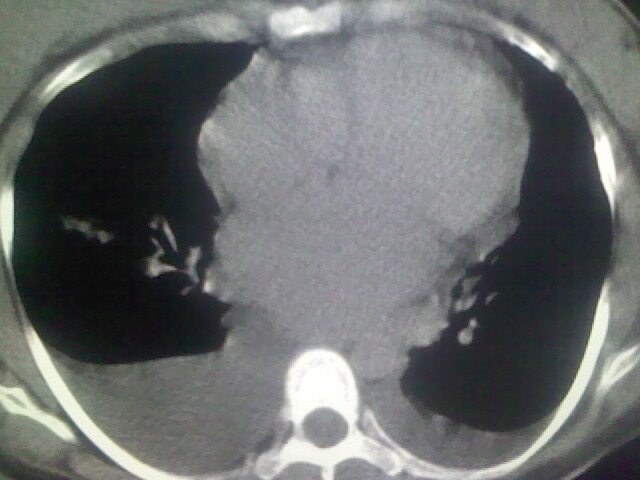

女,24,剖腹产后,突觉胸痛,干咳,不能平卧

胸水 感染 心影增大 肺水肿?

双肺“肺泡性肺水肿” “胸腔积液”!

双侧胸腔积液,肺泡性肺水肿。后纵隔好像有占位。

肝脾大,双侧胸腔积液,双肺水肿,肺动脉[包括远端小动脉],左右心房,左心室增宽,右心室主动脉无明显改变,符合左心功能不全征;;建议除外二尖瓣关闭不全,扩张性心肌病